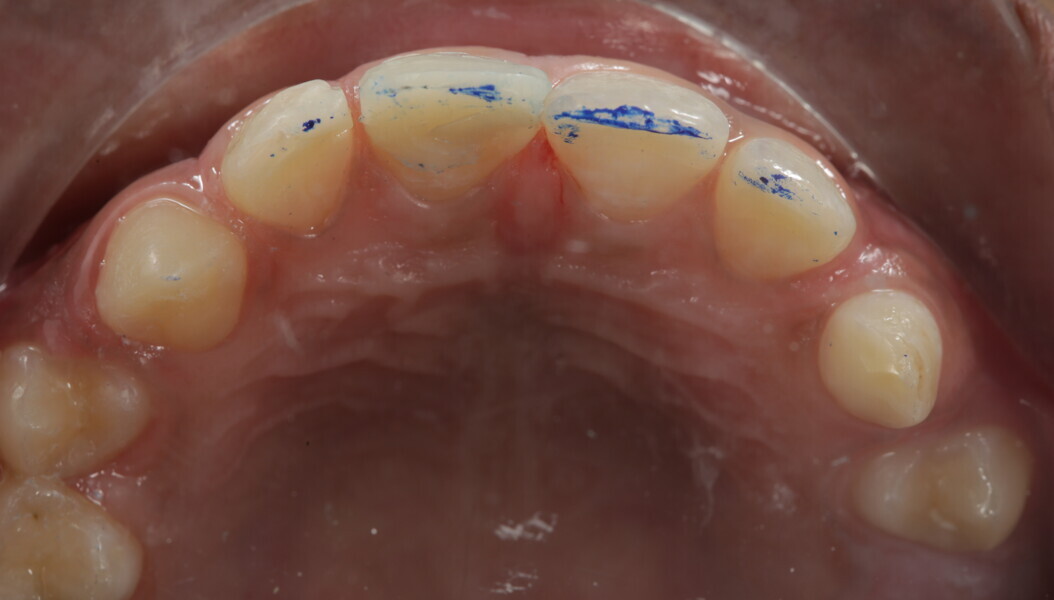

A 10-year-old male patient reported with a complaint of trauma to the upper left central and lateral incisors, involving the enamel and dentin. Direct composite was used in multi-layers and the smile was restored. This article explains detailed steps in the polychromatic layering technique with special emphasis on the finishing and polishing protocol. 3M Espe Filtex Z350 Xt was used with a universal bonding agent.

Fig 25-30: Layering protocol step by step

Fig 31-41: Polishing protocol and post-op